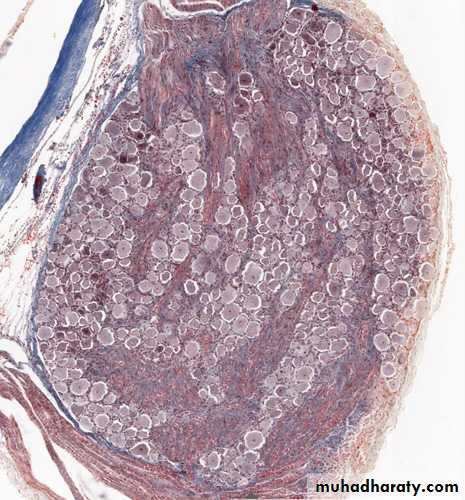

A sensory ganglion (G) has a distinct connective tissue capsule (C) and internal framework continuous with the epineurium and other components of peripheral nerves, except. Fascicles of nerve fibers (F) enter and leave these ganglia. X56. Kluver-barrera stain.